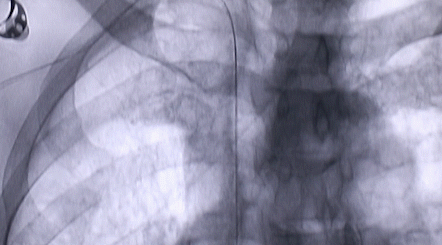

1月12日,西安國際醫(yī)學中心醫(yī)院心臟外科郭穎強主任團隊成功為一名腹主動脈閉塞、右側(cè)腎動脈閉塞、左側(cè)腎動脈重度狹窄、腹壁淺表動脈側(cè)支循環(huán)形成、高血壓病3級(極高危組)合并閉塞性周圍動脈粥樣硬化、急性腎功能不全的老年患者實施腎動脈球囊擴張 腎動脈支架植入術 動脈血栓抽吸術 髂動脈開通術,治好了困擾患者多年的頑固性高血壓?;颊吣壳翱祻土己茫瑢⒂诮粘鲈?。

按照術前制定的方案,郭穎強主任和楊金保博士首先嘗試開通閉塞的右腎動脈,但由于血栓機化、鈣化嚴重,右腎動脈難以開通。遂謹慎擴張狹窄的左腎動脈,并成功植入一枚支架。之后經(jīng)過反復旋磨、抽吸,順利開通髂動脈,但腹主動脈閉塞段仍難以擴通。此時,患者居高不下的血壓很快恢復到正常水平。